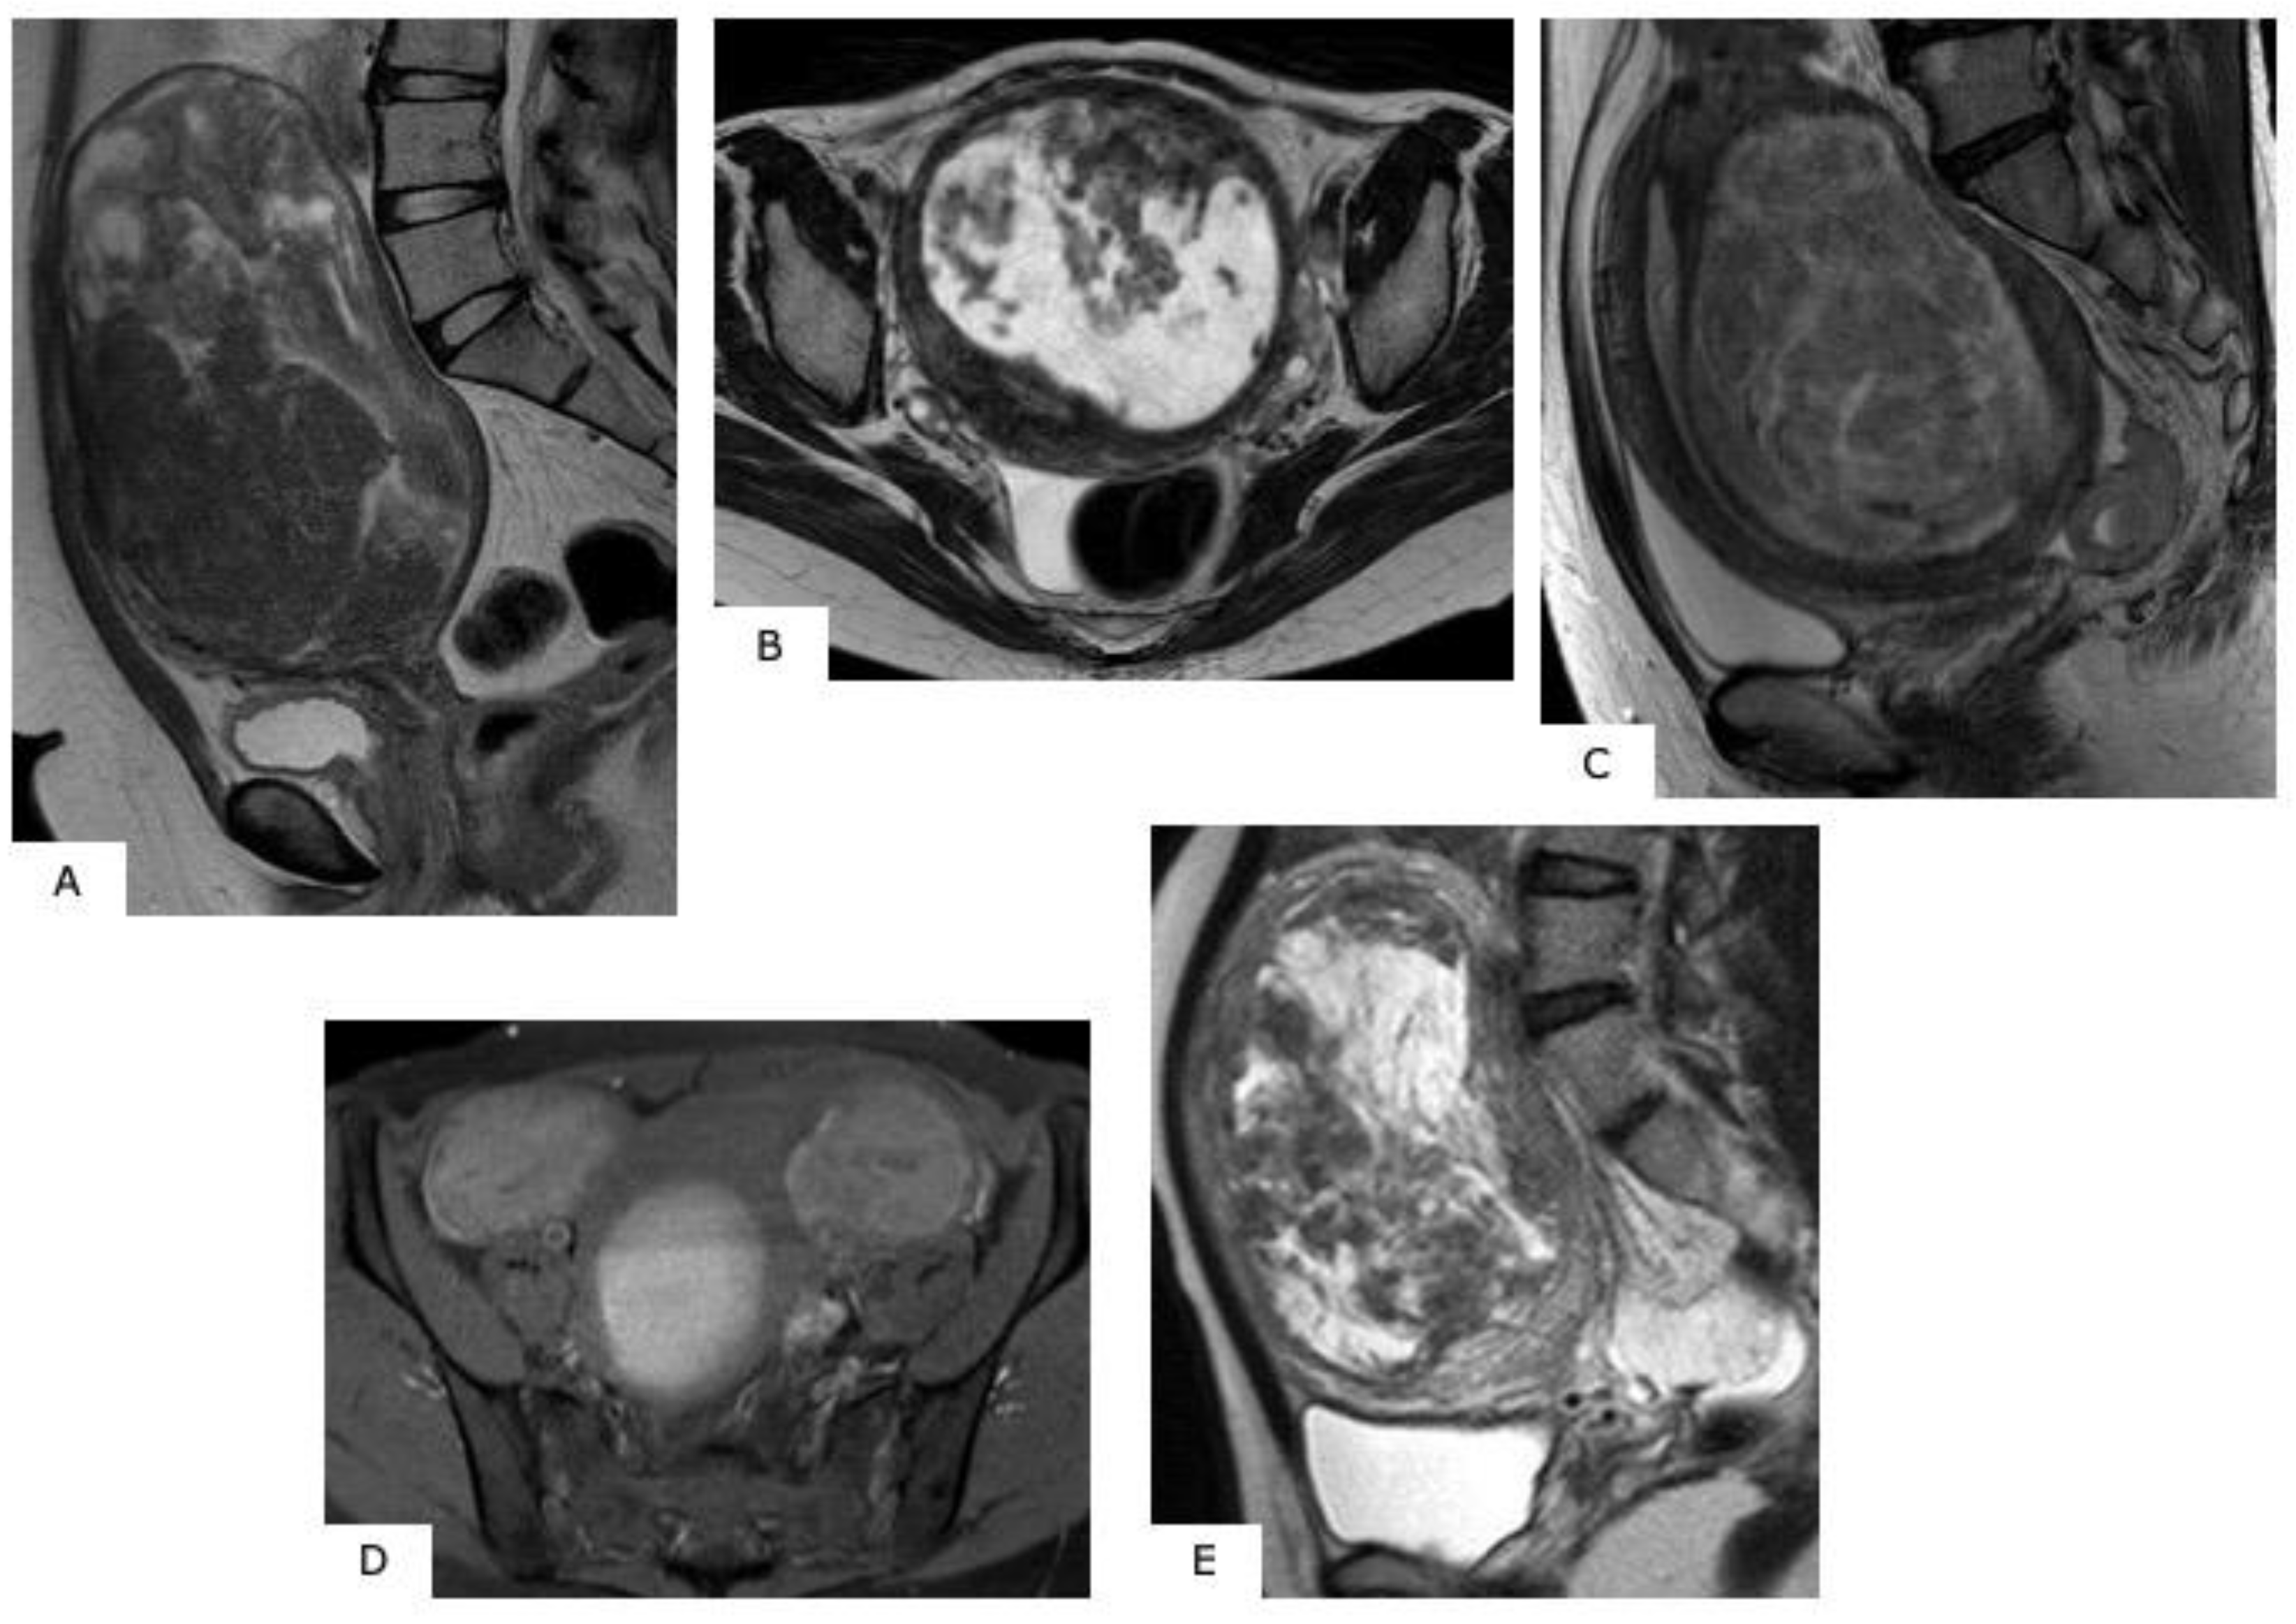

6. MR Images of Uterine Sarcoma

6.1. Characteristic MR Image Findings for Uterine Sarcoma

6.2. Leiomyosarcoma

6.3. Endometrial Stromal Sarcoma (ESS)

7. Differentiating between Uterine Myoma and Sarcoma